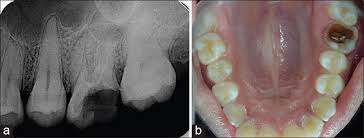

* Example of the case can approve for post & core : tooth#16

*Example of accepted post & core (there is NO space ).